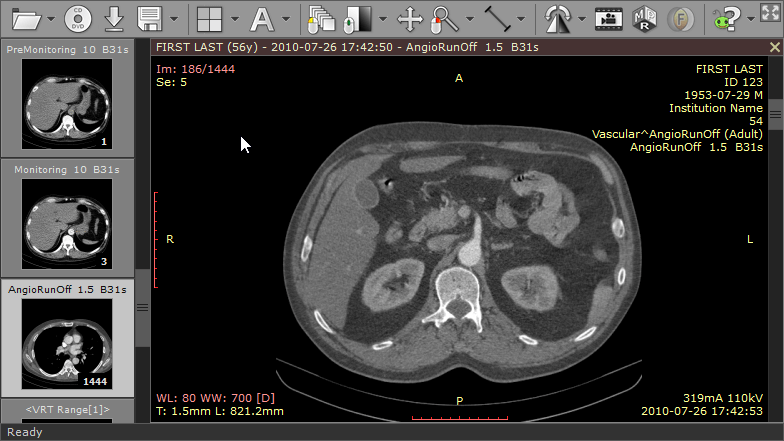

The RadiAnt DICOM image viewer is a simple, fast platform that is compatible with Windows. It offers multiple features, including MPR, MIP, and image fusion. Images can be exported to JPEG, PNG, and other image formats. They can also be copy-pasted directly to presentations and word documents.

The application is just a viewer and does not offer storage space. Their website has a disclaimer explicitly stating that they do not have any certifications, and as such, the product is not intended for diagnostic use. However, it is handy for students and residents for studying medical images and research purposes.

| 3. | RadiAnt | Windows | Not available | Y | Y | Y | Image files, Word and PowerPoint | 5 MB | Intel Multicore/ 2 GB RAM; Resolution 1064x768 | Free version valid for three months only |